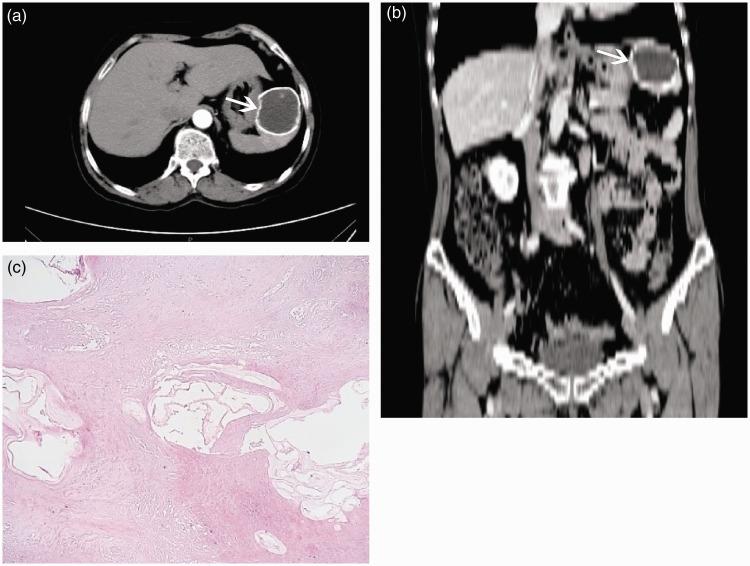

We herein report a case of primary splenic hydatidosis to provide data regarding the diagnosis, treatment, and epidemiological statistics of this disease. The patient was from a pastoral area and was diagnosed with primary splenic hydatidosis with chronic atrophic gastritis. The patient had no history of surgical treatment of hydatidosis. The diagnosis was mainly based on possible exposure to endemic areas, imaging findings, serological test results, and operative and pathological examination findings. Laparoscopic splenectomy was performed, and regular albendazole therapy was given after the operation. The patient was admitted to the hospital for gastrointestinal bleeding 3 months postoperatively, and she was successfully treated and discharged. No recurrence of hydatid foci has been observed since the follow-up.

我们在此报告一例原发性脾包虫病病例,以提供有关该疾病的诊断、治疗及流行病学统计数据。患者来自牧区,被诊断为原发性脾包虫病合并慢性萎缩性胃炎。患者无包虫病手术治疗史。诊断主要基于可能接触流行地区、影像学检查结果、血清学检测结果以及手术和病理检查结果。实施了腹腔镜脾切除术,术后给予常规阿苯达唑治疗。患者术后3个月因消化道出血入院,经成功治疗后出院。随访至今未观察到包虫病灶复发。